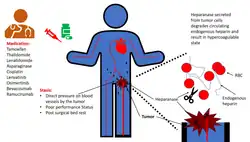

Causes of disturbed blood flow include stagnation of blood flow past the point of injury, or venous stasis which may occur in heart failure,[35] or after long periods of sedentary behaviour, such as sitting on a long airplane flight. Also, atrial fibrillation, causes stagnant blood in the left atrium (LA), or left atrial appendage (LAA), and can lead to a thromboembolism.[35] Cancers or malignancies such as leukemia may cause increased risk of thrombosis by possible activation of the coagulation system by cancer cells or secretion of procoagulant substances (paraneoplastic syndrome), by external compression on a blood vessel when a solid tumor is present, or (more rarely) extension into the vasculature (for example, renal cell cancers extending into the renal veins).[35] Also, treatments for cancer (radiation, chemotherapy) often cause additional hypercoagulability.[35] There are scores that correlate different aspects of patient data (comorbidities, vital signs, and others) to risk of thrombosis, such as the POMPE-C, which stratifies risk of mortality due to pulmonary embolism in patients with cancer, who typically have higher rates of thrombosis.[39] Also, there are several predictive scores for thromboembolic events, such as Padua,[40] Khorana,[41][42] and ThroLy score.[43]